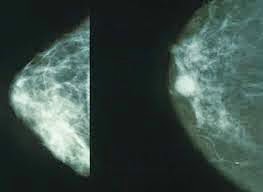

2. มะเร็งเต้านม

โรคมะเร็งเต้านมเกิดจากเนื้อเยื่อของเต้านมมีการเปลี่ยนแปลงเป็นเซลล์มะเร็ง ซึ่งอาจจะกิดเป็นมะเร็งเต้านมที่เกิดกับท่อน้ำนม หรือมะเร็งเต้านมที่เกิดกับต่อมน้ำนม มะเร็งเต้านมเป็นมะเร็งที่พบได้บ่อยดังนั้นท่านผู้อ่านที่เป็นหญิงหรือชายควรจะตรวจเต้านม

ตัวเอง

มะเร็งเต้านมเป็นมะเร็งที่พบมากที่สุดในผู้หญิง จากสถิติของสถาบันมะเร็งแห่งชาติพบผู้หญิงเป็นมะเร็งเต้านมร้อยละ 37 ของมะเร็งทั้งหมด และยังมีอัตราการเสียชีวิตเป็นอันดับสองรองจากมะเร็งปอด ดังนั้นการดูแลตัวเองเพื่อลดความเสี่ยงของการเกิดมะเร็ง และการค้นพบมะเร็งตั้งแต่ระยะเริ่มแรกในขณะที่ก้อนมีขนาดเล็ก และก้อนมะเร็งยังอยู่เฉพาะที่เต้านม ยังไม่แพร่กระจายไปต่อมน้ำเหลือง จึงเป็นเรื่องสำคัญ เพราะ จะมีโอกาสหายขาดมากขึ้น เมื่อเทียบกับการตรวจพบก้อน มะเร็งที่มีขนาดใหญ่ หรือกระจายไปต่อมน้ำเหลืองที่รักแร้แล้ว โดยหากมีการตรวจพบมะเร็งเต้านมในระยะเริ่มต้น มีโอกาสที่จะมีชีวิตเกิน 5 ปีถึงร้อยละ 98 ถ้าตรวจเจอ ตอนก้อนมะเร็งกระจายไปที่ต่อมน้ำเหลืองที่รักแร้แล้ว มีโอกาสที่จะมีชีวิตเกิน 5 ปีร้อยละ 84 และถ้าตรวจเจอ ตอนมะเร็งแพร่กระจายไปแล้ว โอกาสที่จะมีชีวิตเกิน 5 ปี มีเพียงร้อยละ 23 และยังไม่แพร่กระจายจะทำให้มีโอกาศรอดชีวิตสูง ก้อนขนาดเล็กก่อนที่จะรู้เรื่องมะเร็งท่านต้องทราบ

1. การตรวจเต้านมด้วย แมมโมแกรม ซึ่งจัดว่าเป็นวิธีที่ดีที่สุดในการตรวจคัดกรอง มะเร็งเต้านมในผู้หญิงทั่วไป